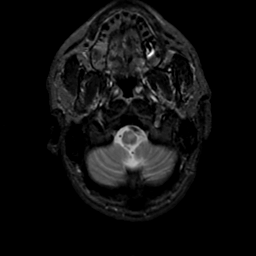

MR Study #18, July 21, 1991 -- Slice #4

[Home][Help][Clinical][Tour 1][Tour 2] Slice 4